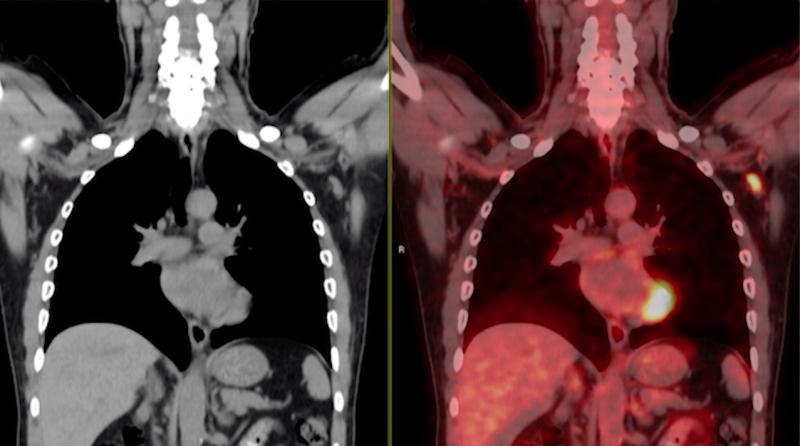

This photo gallery shows the variety of radiological presentations of COVID-19 (SARS-CoV-2) in medical imaging, including computed tomography (CT), radiograph X-rays, ultrasound, echocardiograms and magnetic resonance imaging (MRI). The radiology images show examples of typical COVID pneumonia in the lungs and the numerous complications the virus causes in the body in multiple organs, including the brain, kidneys, heart, abdomen and vascular system.

Ultrasound, especially hand-held ultrasound imaging devices, have become a primary imaging modality for novel coronavirus because of the ease to bag the device and sterilize it after use. CT and mobile X-ray systems are also used as front-line imaging systems for COVID-positive or suspected COVID patients.